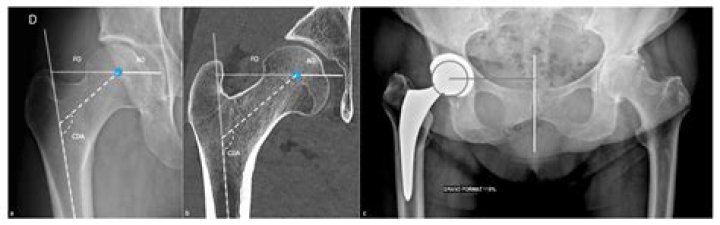

How big is a femoral head?

The natural size of the femoral head usually ranges from 40 to 54 mm, with smaller sizes usually found in females. In the initial development of hip arthroplasty, artificial femoral heads were designed to replicate these anatomical dimensions.